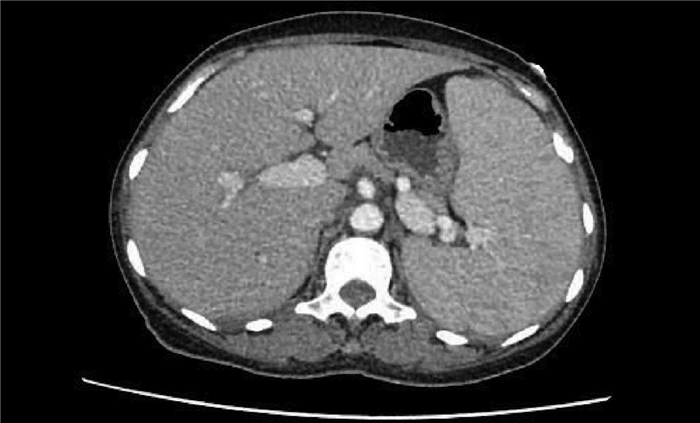

Liver biopsy diagnosis of hepatic extramedullary hematopoiesis: A case report